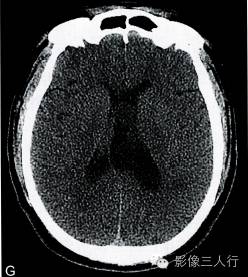

A.T2WI横断面;B.T1WI横断面;CFLAIR冠状面;D、E、F.增强横断面、矢状面、冠状面;G、H.CT平扫、增强;I.HE×100

肿瘤呈类圆形,边界清楚,位于左侧脑室前角及室间孔区,左侧脑室前角、三角部及左侧脑室后角扩张积水。MRI平扫T2WI(图A)肿瘤呈稍高信号,内见小范围高信号区;T1WI(图B)肿瘤呈等信号,内见低信号区;冠状面水抑制相(图C)肿瘤呈稍尚信号,内部原长T1长T2区信号呈低信号;增强扫描(图D~F)肿瘤强化不明显;CT平扫(图G)左侧脑室前角类圆形、边界清楚、较均匀等密度肿块,增强扫描(图H)强化不明显。